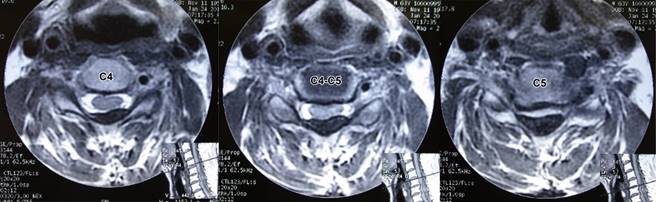

A la exploración inicial: paciente en silla de ruedas, con ausencia de equilibrio de tronco, frecuencia cardiaca de 80 l/min; frecuencia respiratoria de 16 r/min; tensión arterial de 110/60 mmHg, cráneo, cara y cuello al igual que pares craneales normales; tórax con ampliación y amplexación disminuidas, murmullo vesicular normal, ruidos cardiacos rítmicos sin fenómenos agregados; sensibilidad normal a nivel de C4 con hipoestesia profunda por abajo de horquilla esternal; abdomen, blando depresible, sin visceromegalias; reflejos cutáneo abdominales aumentados; miembros superiores con arcos de movimiento pasivos completos; examen clínico muscular para miembro superior derecho con calificación 0/5 de deltoides hacia abajo, miembro superior izquierdo deltoides en 4/5, bíceps braquial, coracobraquial y braquial anterior en 3/5, resto de musculatura en 0/5, por lo que se diagnostica lesión de neurona motora inferior en C5 derecha y C6 izquierda. Reflejos osteotendinosos tricipital, bicipital y estiloradial +++ bilateral; Hoffman bilateral presente; genitales normales, ausencia de reflejo anal; extremidades pélvicas: contractura en flexión de caderas, rodillas y tobillos por espasticidad, hipotrofia muscular generalizada de miembros pélvicos, examen clínico muscular en 0/5 bilateral; reflejos osteotendinosos rotulianos y aquileos +++, sensibilidad ausente. Babinski presente bilateral, conformando una lesión de neurona superior a nivel C6 derecha y C7 izquierda; siendo clasificada como grado V en la escala de Nurick. Se solicitó resonancia magnética mostrando: canal estrecho por presencia de ligamento amarillo hipertrófico de C2 a C7 (Figuras 1 a 3). Considerando tanto al área medular como a la del canal espinal como elipses, se utilizó fórmula para su cálculo (A = π × R1 × R2), así como al índice de Torg-Pavlov para valorar sus relaciones (Tabla 1). Con diagnóstico de mielopatía con nivel motor en C5, C6 y nivel sensitivo C5 derecha y C6 izquierda. Se interviene quirúrgicamente practicando laminectomía de las vértebras C3, C4, C5, C6 y C7 encontrando ligamento amarillo hipertrófico, el cual se reseca en su totalidad de C3 a C7, quedando el saco dural libre y latiendo, cerrando por planos. El estudio de patología reportó: cortes histológicos mostrando múltiples fragmentos de ligamento amarillo con mineralización y pérdida de la periodicidad de las fibras y cambios degenerativos moderados.

Figura 2: Imágenes de resonancia magnética de columna cervical ponderadas en T2 en cortes axiales, mostrando diferentes grados de canal estrecho en los cortes a nivel de C4, espacio C4-C5 y corte en C5, producidos principalmente por hipertrofia del ligamento amarillo.